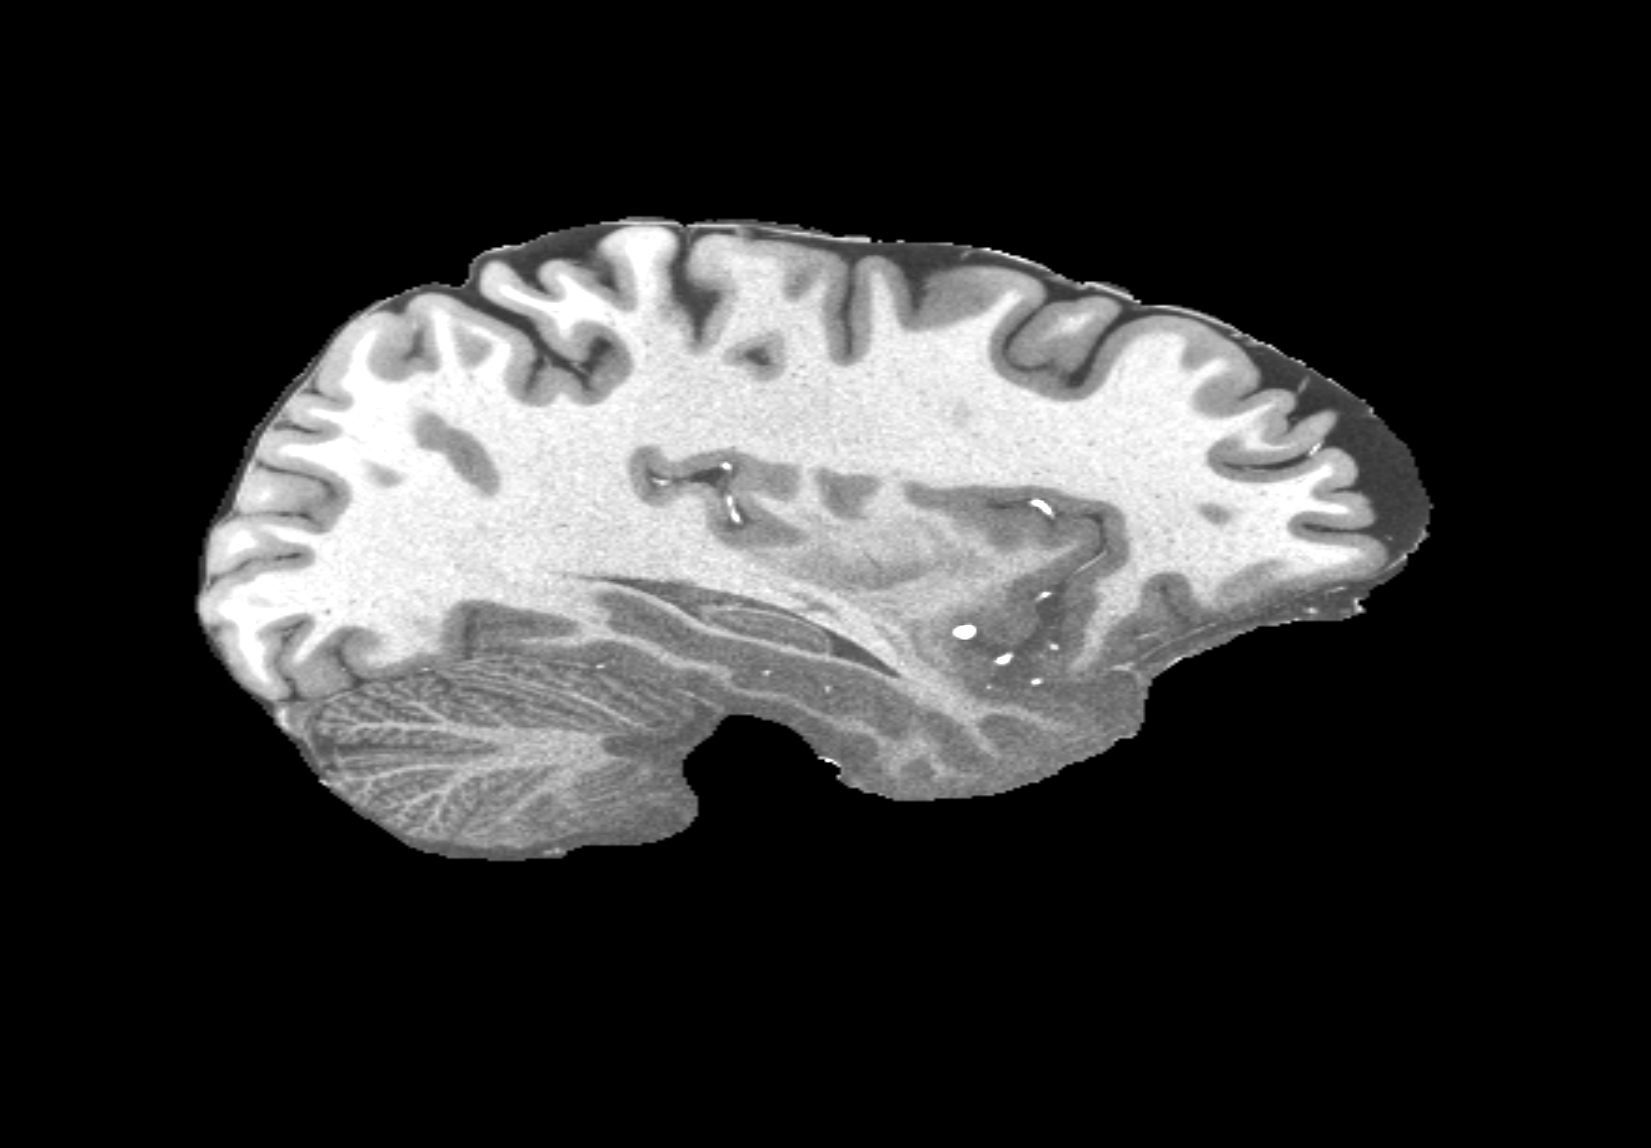

4.2 Registration to a 100 micron ex-vivo brain MRI volume

To showcase the efficacy of our method on real large scale images, we register a 250 in-vivo MRI image (Lüsebrink et al., 2017) to a 100 ex-vivo FLASH human brain volume (Edlow et al., 2019). This represents an inverse problem with more than 11.2B optimizable parameters (compared to 20M for clinical datasets), or 44.8GB of GPU memory. The entire problem does not fit on most GPUs, necessitating distributed multimodal registration. We optimize a composite transform - affine followed by a diffeomorphic mapping; details can be found in Section E.1. Multimodal deformable registration took 58 seconds on 8 NVIDIA A6000 GPUs, which is unprecedented at this resolution. Fig. 6 shows qualitative results, highlighting the ability to register highly detailed structures such as cerebellar white matter; these structures are not visible at macroscopic scales. The resultant advantages of performing registration at this scale can allow researchers to characterize the neuroanatomy at microscopic resolutions and allow morphometric analysis of cortical layers and subcortical nuclei among other structures.